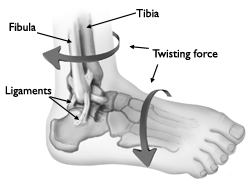

Siła skrętna działająca na stopę, zazwyczaj powoduje złamanie w obrębie kostki, a także zerwanie bądź naderwanie więzadeł i uszkodzenie torebki stawowej.

Do urazu stawu skokowego dochodzi zazwyczaj podczas uprawiania sportów lub innych ruchowych aktywności, podczas których stopa ulega nagłemu skręceniu. Dzieci uprawiające sporty, które wymagają supinacji stopy i podskoków (piłka nożna, koszykówka), są bardziej narażone na złamanie w obrębie kostki.